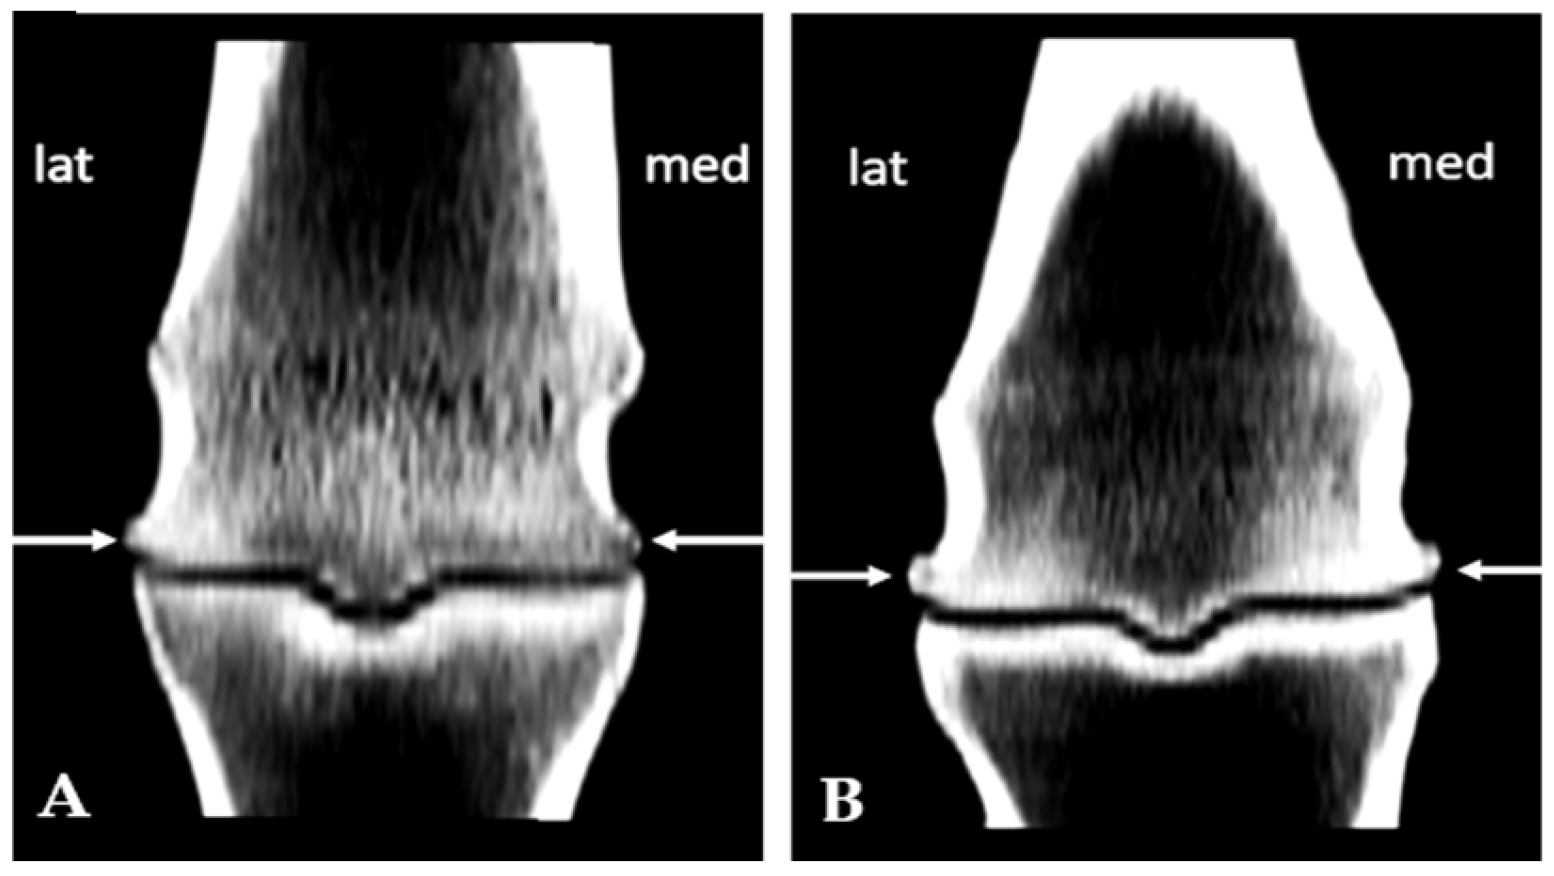

3.1. Subchondral Sclerosis Presence

3.2. Osteophytes Presence